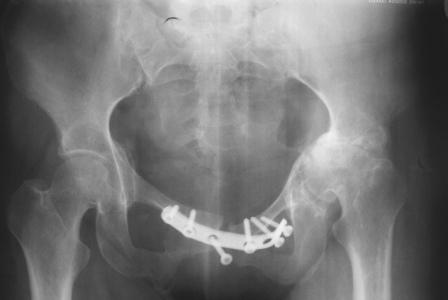

Уважаемые коллеги! Пациентка 32 года с застарелым повреждением таза, после остеосинеза лонного сочленения пластиной. Посоветуйте с выбором тактики и методик лечения.

Получила травму в феврале 2004г в г.Лобытнанги ЯНАО Тюм.обл. Через неделю после поступления выполнен остеосинтез лонного сочленения пластиной. 1,5 месяца на скелетном вытяжении. В последующем ходит при помощи костылей с нагрузкой на правую ногу. Имеется нестабильность половин таза, неправильно-консолидированный перелом левой вертлужной впадины, невропатия седалищного нерва слева. В результате невропатии седалищного нерва сформировалась эквинусная установка левой стопы, парестезии по подошвенной поверхности.

Направлена к нам для устранения патологической установки стопы и эндопротезирования левого тазобедренного сустава, также имеется миграция шурупов пластины, фиксирующей лонное сочленение.

Клинически: ходит на костылях с нагрузкой на правую ногу. Левая стопа в эквинусе. Осевая нагрузка на левую н\конечность болезненна в области левого тазобедренного сустава, при прикосновениях к подошвенной поверхности стопы у пациентки чувство зжения. В левом коленном суставе полный обьем движений, в левом тазобедренном резко ограничено отведение и ротация, укорочение левой н\конечности на 2,5 см. При полипроекционной и функциональной Р-графии выявлена нестабильность левого КПС и лонного сочленения, консолидированный в порочном положении поперечный оскольчатый перелом левой вертлужной впадины с центральным смещением головки бедра. Нами выполнена коррекция деформации левой стопы. Планируется выполнить введение 2 канюлированных илиосакральных винтов слева, реостеосинтез лонного сочленения реконструктивной пластиной, после заживления ран - тотальное эндопротезирование левого тазобедренного сустава.

Вопросы: 1. достаточно-ли предпологаемой фиксации тазового кольца, может быть добавить аппарат внешней циксации;

2. сроки установки эндопротеза;

3. методика установки вертлужного компонента.